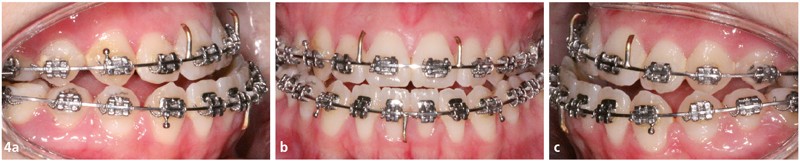

Traitement multi-attaches (fig. 4, 5, 6 et 7)

Les extractions orthodontiques ont été réalisées avant le collage de l’appareillage multi-attache Roth 022x.028.

Une séquence d’arcs Niti (.014, .018, .018x.025) a permis de réaliser l’alignement et le nivellement de l’arcade mandibulaire, avant de passer en acier (.019x.025).

La séquence d’arcs a été différente au maxillaire : un acier .014 en by-pass sur les incisives latérales a dans un premier temps été mis en place afin d’éviter tout effet néfaste de vestibuloversion.

Ensuite un arc avec des boucles de fermeture acier .018 a été utilisé afin de permettre le rabitting compte tenu de l’encombrement majeur.

Une fois les espaces d’extractions fermés, nous avons poursuivi le nivellement avec des arcs aciers .016x.022 puis .018x.025 afin de programmer la chirurgie orthognathique.